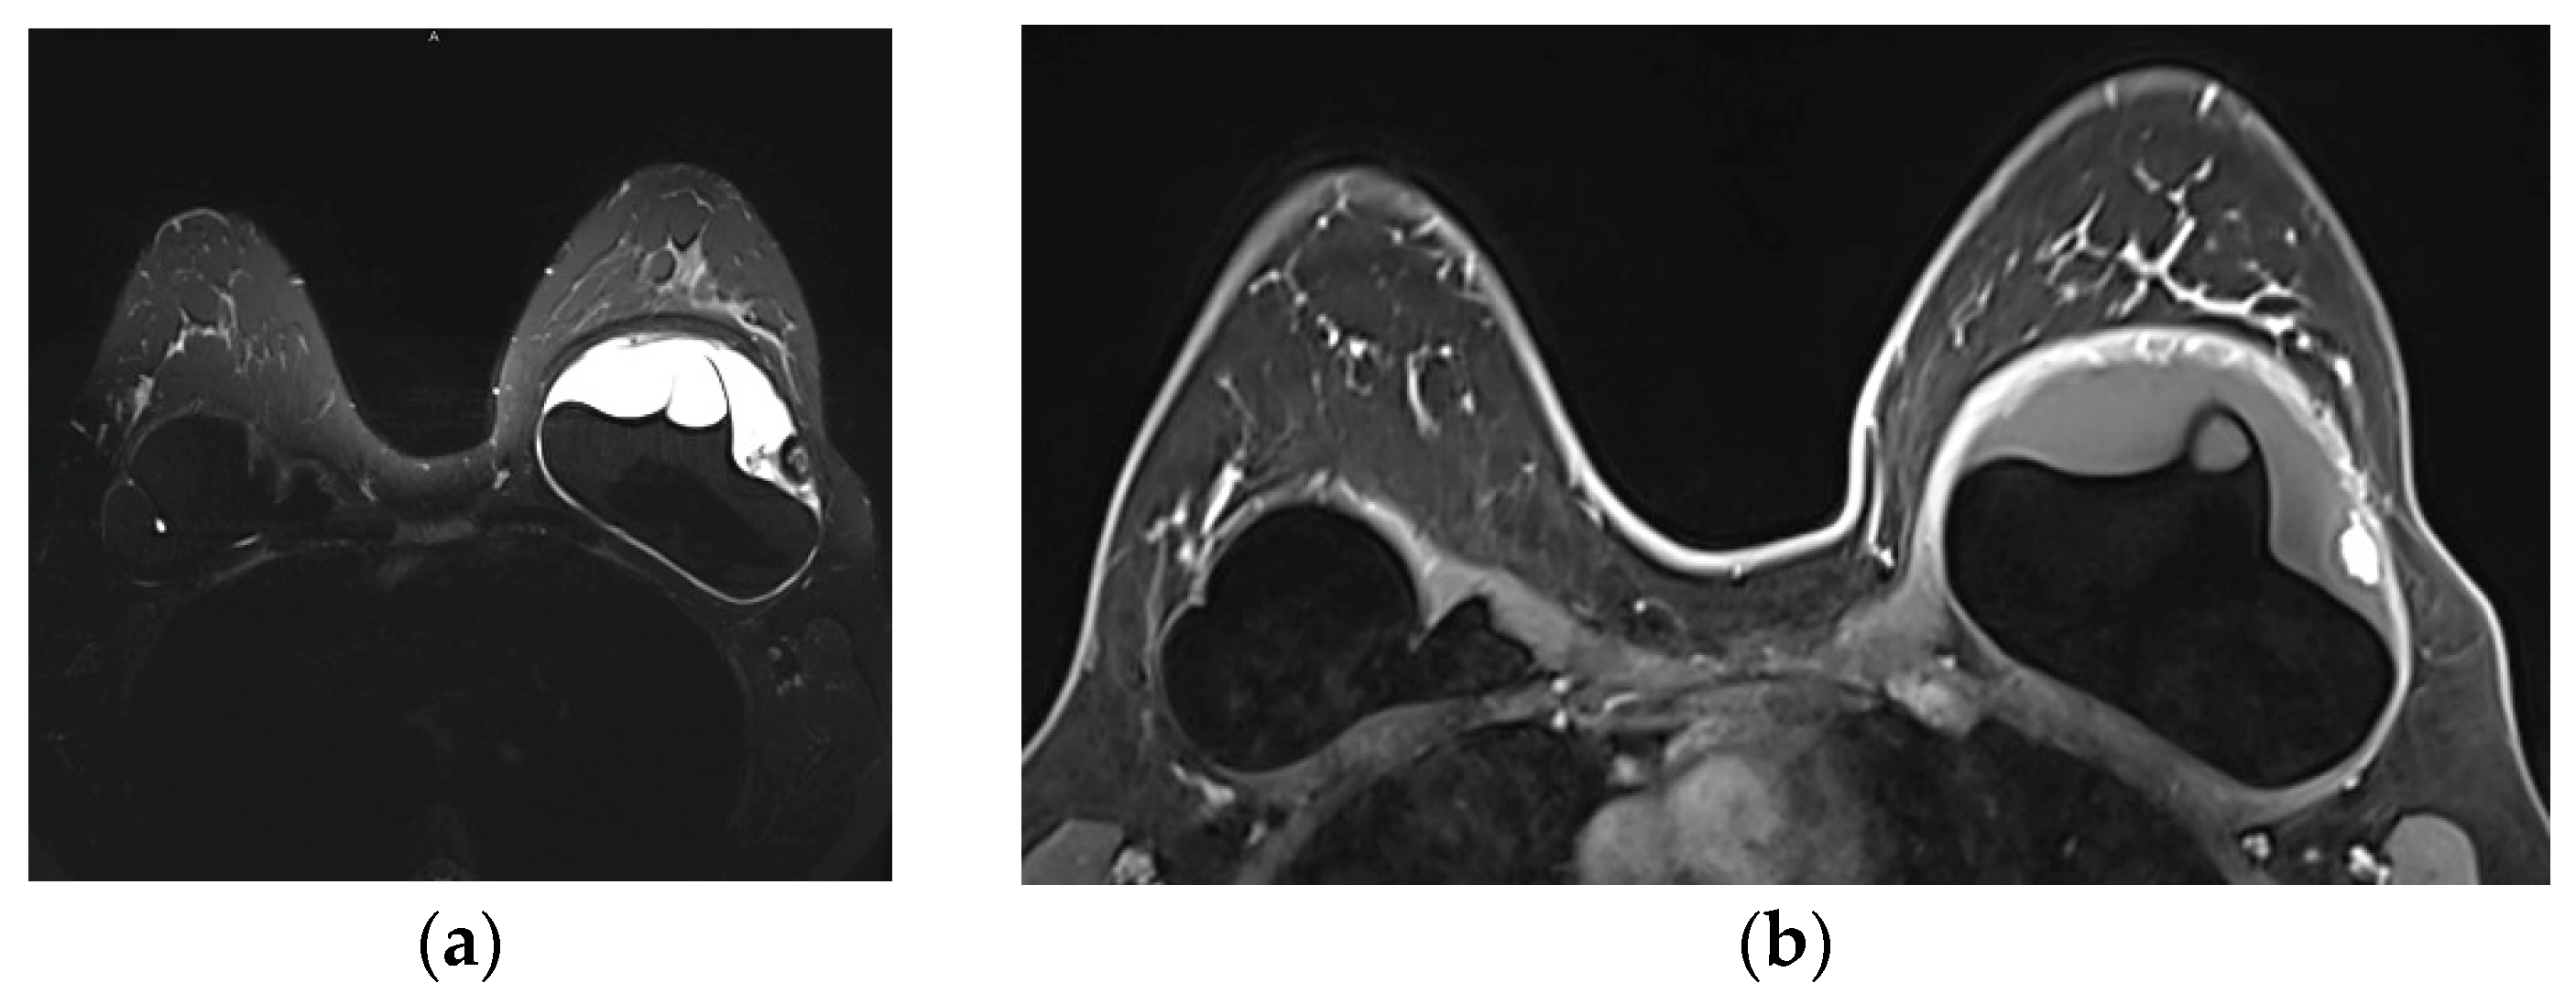

The typical mammographic appearance of an implant is a radiopaque oval mass with smooth margins whose density varies depending on the filling material (Figure 3a). A band of soft density tissue surrounding the implant, with or without calcifications represents the thick fibrous capsule that is formulated after the implant insertion as a result of a foreign body reaction. Folds within the implant and the valve may be visible with the appropriate mammographic technique [47].

Ultrasonographically both saline and silicone implants are anechoic and the shell appears either as one echogenic line or as parallel echogenic lines. Internal folds may be recognized as wavy lines without disruption. The fibrous capsule is visible as an echogenic line parallel to the implant’s shell, sometimes with calcifications producing focal acoustic shadowing (Figure 3b). A small peri-implant fluid effusion is a normal finding. At implants with expanders the valve is visible and caution should be taken so that partially expanded implants should not be mistaken for ruptured implants [47].

Figure 3. Mediolateral oblique MLO mammography view and ultrasound (US) of the right breast after mastectomy and reconstruction with a single lumen silicone implant (a) At the MLO view the implant appears as a homogenous radiopaque oval mass with smooth borders; (b) On US the implant is anechoic. The intact shell appears as echogenic line (yellow arrows) and the fibrous capsule is seen as a parallel echogenic line (red arrows).